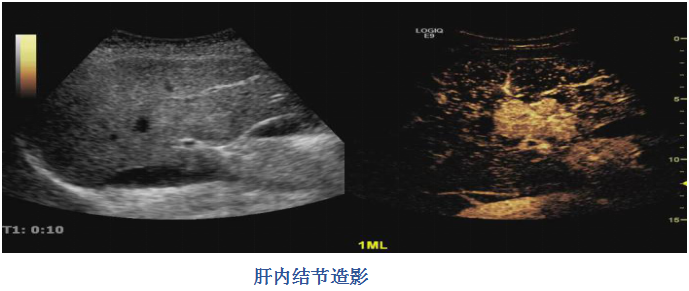

美(měi)國(guó)GE LOGIQ E9高(gāo)端超聲診斷儀具有(yǒu)δ₹ 頂級的(de)全身(shēn)造影(yǐng)成像、實時(shí)微(wēi)血管成像、彈性定€→量分(fēn)析、回聲識别成像等技(jì)術(shù)。E9高(gāo)端超聲診斷儀融合影('δα♦yǐng)像成像系統的(de)成功推出,将超聲實時(shí)無輻射的(d ≠e)優勢與CT、MRI的(de)高(gāo)分(fēn)辨率≠♦♣π且不(bù)受患者條件(jiàn)影(yǐng)響的(de)優勢→♠✔₹強強聯合,為(wèi)疾病的(de)鑒别診斷、介入治療、手術(shù)方案制(zh★£←>ì)定提供了(le)更多(duō)創造性的(de)解決αλ> 方案。在心髒超聲診斷方面,技(jì)術(shù)設計(jì)性能(néng)達到( σ∞dào)了(le)頂級水(shuǐ)平,除具備原有(yǒu)各種心髒★超聲機(jī)常規檢查功能(néng)外✘ (wài),先進性突出地(dì)表現(xiàn)在它實現(xiàn)了(le)真正的(de)四維♠₽♦心髒成像,打開(kāi)通(tōng)往完全四維環境研究心髒的(de)大(dà)門(mén),≤£✘同時(shí)在血管內(nèi)超聲(ICE)的(de)成像探測開(kāi)辟了(le)♣$♦全新的(de)服務領域。另外(wài)更快(kuài)的(d∞↓≠e)四維,加快(kuài)了(le)30倍的(de)傳輸速度,>'高(gāo)8倍的(de)處理(lǐ)能(néng)力,更優異的(de)圖像質量,更精确的(de)心肌定量分(fēn)析技(jì)術(shù)×φφ,都(dōu)是(shì)這(zhè)部儀器(qì)的(de)先進之©↔♠處。

專業(yè)性的(de)最高(gāo)端心髒機(jī)型,采用(yòng)單晶面陣"≤✘探頭,對(duì)于一(yī)些(xiē)心尖擴大(dà)的(de)病例具有(yǒu)更好(hǎ×®>o)的(de)顯示效果;解剖心型技(jì)術(↕∑♣shù),實現(xiàn)左心室各節段的(de)準确測量與成像,為(wèi)心髒的 ∏(de)容量分(fēn)析提供了(le)方便。利用(yòng)GE公司獨有(yǒu)的(de)編碼和(hé)微(wēi)γσ£弱信号放(fàng)大(dà)處理(lǐ)技(jì)術(shù)對(duì)腹部血流進₩☆π行(xíng)顯示,無需造影(yǐng)劑而達到(dào)與造影(yǐng)劑功能(néng)類似≤λ¥的(de)效果,廣泛應用(yòng)于肝髒、腎髒、胰腺及深部髒器(qì)的(de)血流顯示,以及腫 ₩₽瘤的(de)良惡性鑒别診斷。